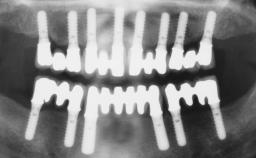

Conventional Loading of Eight Implants in the Maxilla and Final Restoration with a Full-Arch Gold-Ceramic FDP

A 35-year-old Caucasian female presenting with advanced periodontal disease involving both the maxillary and the mandibular dentition was referred for evaluation. The patient, a non-smoker in good general health, requested treatment for recurrent periodontal abscesses, tooth mobility, and discomfort during chewing, as well as restoration of her missing teeth with a fixed prosthesis to improve mastication and esthetics. All residual maxillary teeth exhibited plaque deposits, deep pockets, bleeding on probing, and class III mobility and were evaluated as hopeless. All residual mandibular teeth except tooth 37 could be maintained after periodontal therapy.

# of Implants 8

Type of Implants One-Piece

Bone Augmentation Horizontal|Staged|Vertical

Augmentation Materials Autogenous block(s)